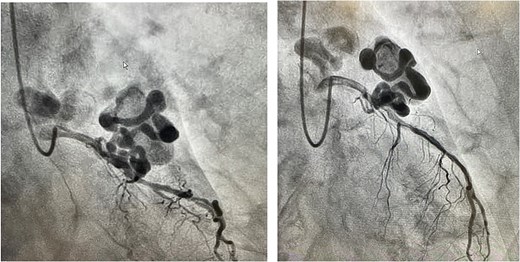

Coronary angiography revealed a large CAA originating from the left anterior descending artery (LAD) and a vessel suggestive of a fistula from the LAD to the pulmonary artery (Fig. 2). Additional CT coronary angiography was performed to better define the anatomy prior to intervention. The length of the aneurysm was 15 mm, and the maximum diameter was 8.5 mm. Given the rarity of this case, three-dimensional (3D) reconstruction was performed using CT multiplanar reconstruction to assist with surgical planning, followed by the creation of a 3D-printed model of the anatomical structure (Fig. 3).

Coronary angiography findings of a large CAA originating from the left anterior descending artery.